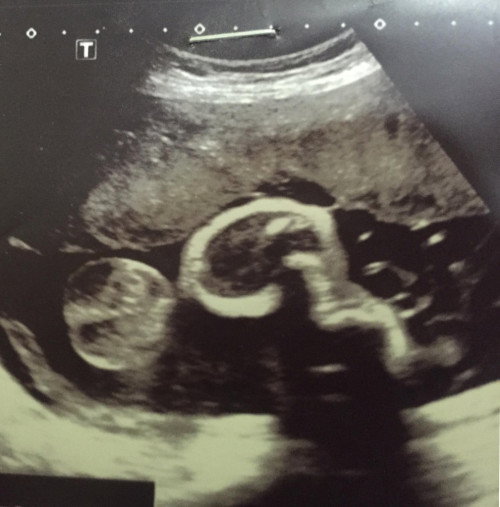

รบกวนช่วยดูให้หน่อยค่ะ ว่าน้องเป็น หญิง หรือ ชาย

ใกล้คลอดแล้วหมอยังไม่ได้แจ้งเลย ใครพอดูเป็นบ้างคะ